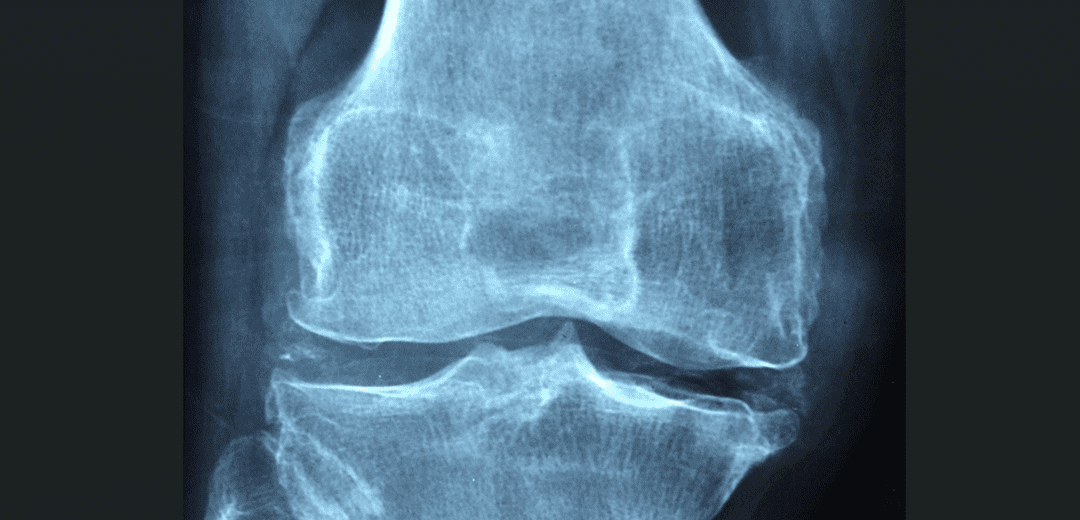

1. 관절염

관절염은 관절 주변 조직의 염증으로 인해 발생하는 통증을 초래합니다. 이는 면역 시스템의 과도한 반응 또는 자가면역 질환에 기인하여 관절 내부의 연골 파괴와 염증을 유발합니다. 이로 인해 관절이 뻐근하고 통증이 발생하며, 움직임에 제한이 생깁니다.